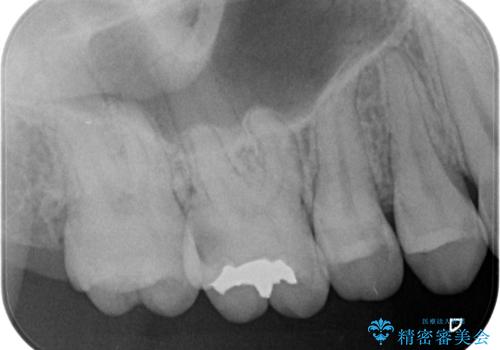

奥歯の虫歯の治療

- 奥歯が虫歯になっていたため治療しました。

手前側の歯は前から見えるため、セラミックの詰め物で治療しました。

奥は高さを取るのが難しかったため薄く作れる金属(ゴールド)で治療しています。

- 合計 26.4万円(内訳:右上7 PGAクラウン 11万円(旧料金)、右上6PGAインレー 7.7万円(旧料金)、右上5 emaxインレー 7.7万円)費用は治療当時の料金となります